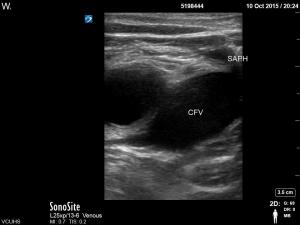

C. Clip of Saphenous Vein joining Common Femoral Vein with compression